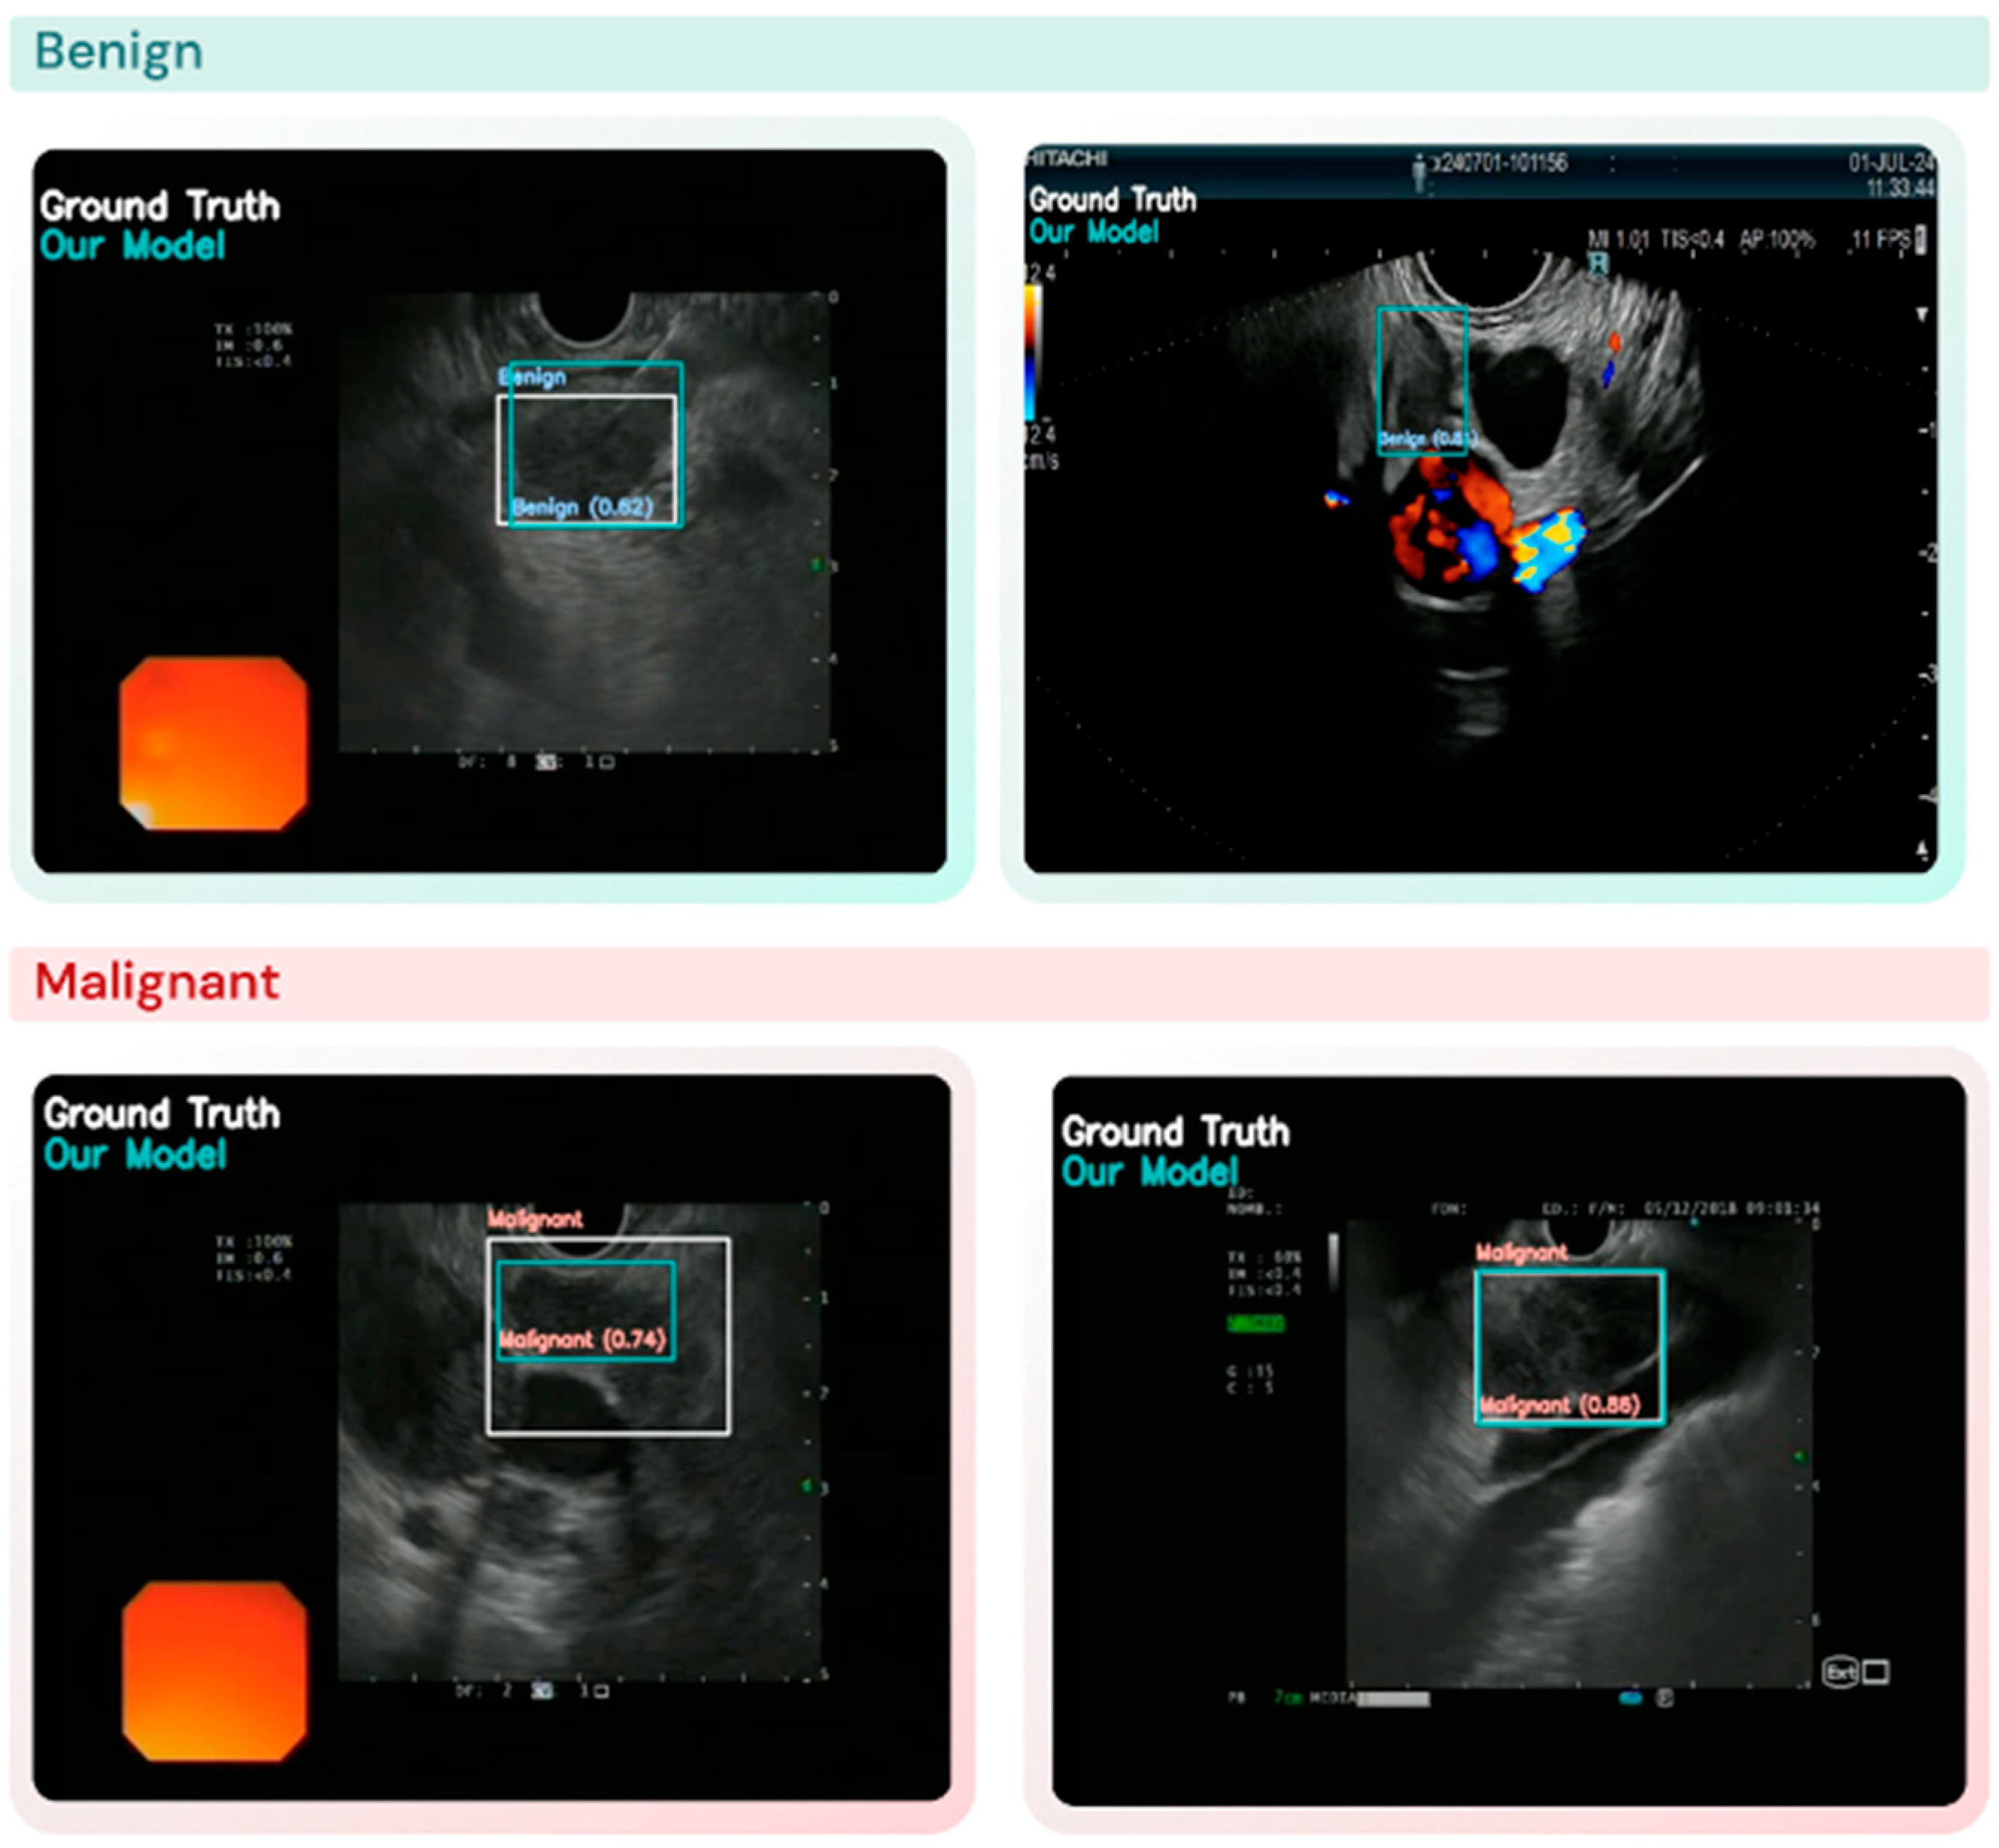

3.2. Lymph Node Detection and Classification Performance